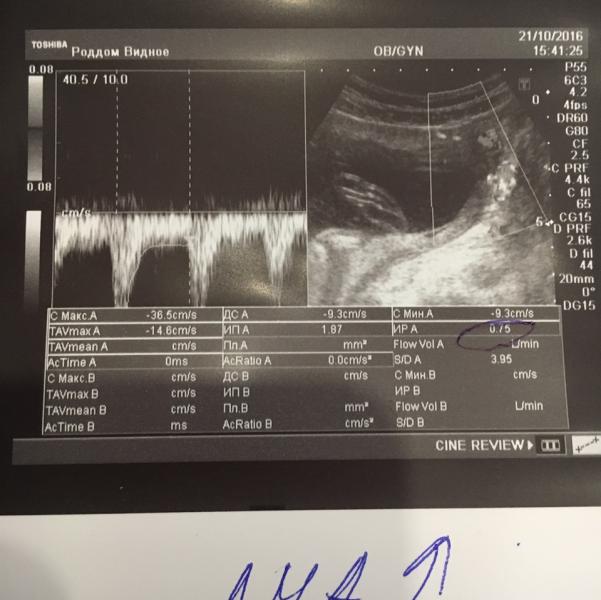

Девочки, кто понимает в допплерометрии? Сегодня была на втором скрининге, срок 20,2 нед. Повышен левый маточный кровоток. Это опасно для малыша? Как вас лечили?

@jizn29, да, потому что в первый скрининг с левым кровотоком тоже было не все хорошо, вот он не нормализовался и ко второму 😔

Подскажите как беременность протекала? У меня сейчас такая же фигня😭 повышен кровоток в левой маточной артерии и ставят нарушение 1а